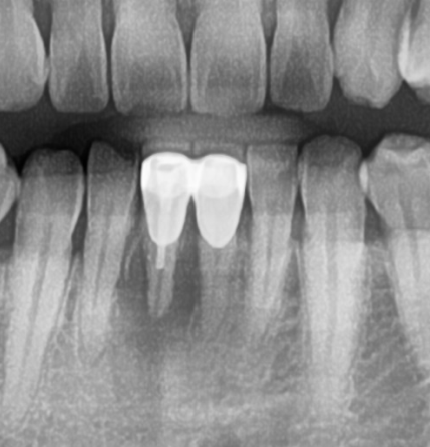

과거에 한 아래 앞니 브릿지의 지대치의 잇몸뼈가 모두 흡수되어 아프고 보기 싫다고 내원 하신 40대 남성분.

엑스레이 검사 후 아래 앞니 하나는 발치하고 브릿지로 재치료 하기로 계획하였습니다.